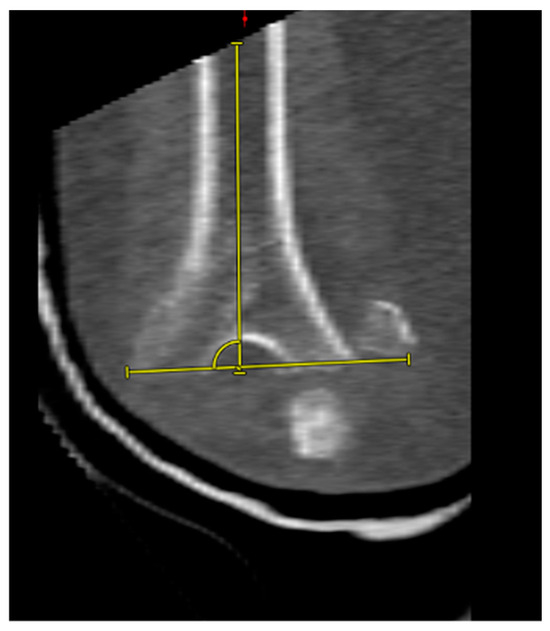

2.3. Conventional CT

2.4. CT Image Analysis